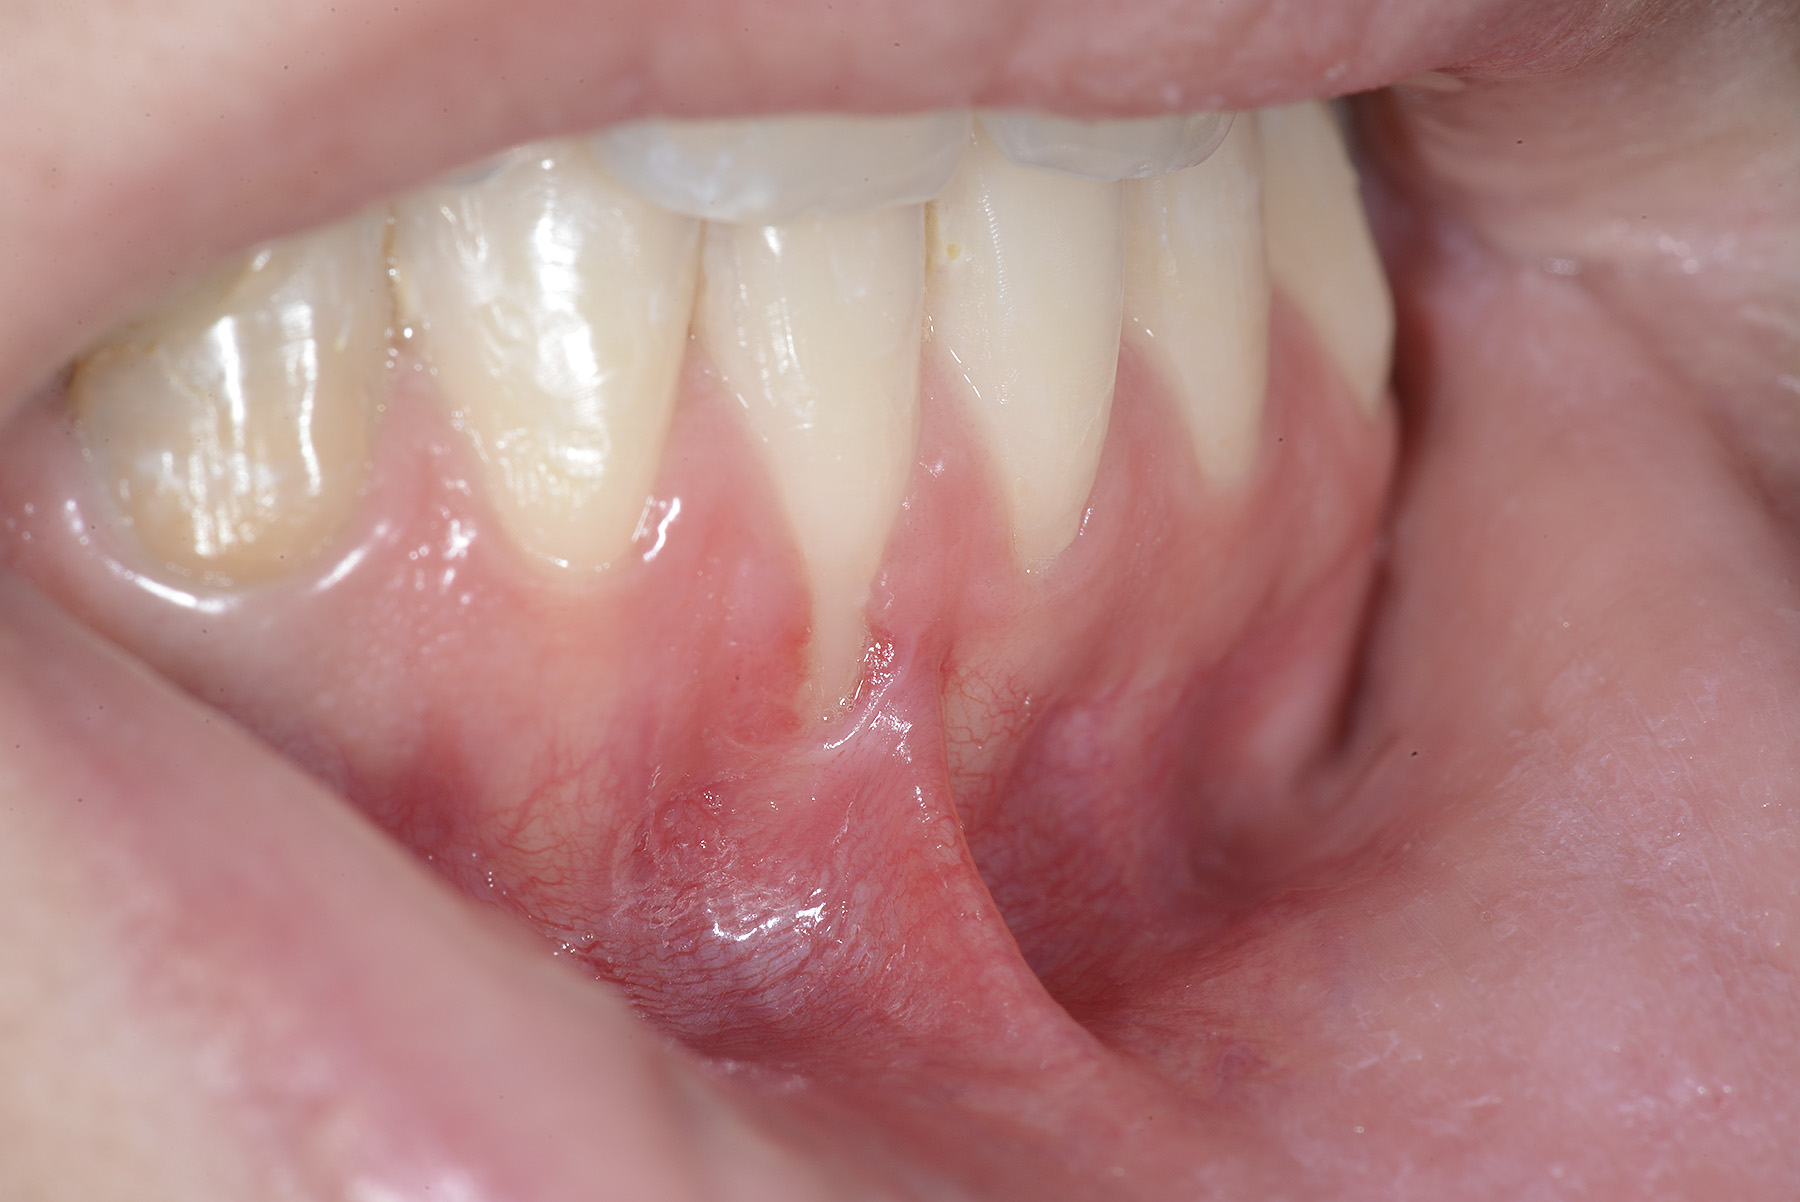

PREMESSA: in seguito all’estrazione dell’incisivo laterale superiore di destra, resasi necessaria per cause batteriche, si decide di affrontare il caso con il posizionamento di un impianto in sostituzione dell’elemento mancante dopo guarigione del sito infetto. Con tecniche rigenerative sia dei tessuti ossei mancanti a causa dell’infezione pregressa, sia dei tessuti gengivali che appaiono inizialmente troppo spostati in alto, si ripristina una corretta morfologia delle parabole (contorni) gengivali e delle papille interdentali (triangoli di gengiva tra due denti vicini).